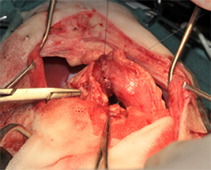

病名:肝細胞癌 手術法:内側右葉完全肝葉切除術

症例:11歳 避妊雌 MiX犬 12kg

主訴:1週間前から食欲の低下と嘔吐で来院されました。

検査:腹部超音波検査にて肝臓内側右葉に直径約12cm大の肝臓腫瘍が認められました。また、胆のうに重度の胆泥の貯留を認めました。

治療:飼い主様の希望により、肝臓腫瘍摘出手術と胆嚢切除手術行いました。肝臓腫瘍摘出は特に血管系の処理が重要で基本的な結紮技術はもちろん、超音波乳化吸引装置や血管シーリング装置などを駆使し血管を一つずつ処理して行きます。

肝臓腫瘍と胆嚢を摘出した写真です。肝臓腫瘍摘出には超音波乳化吸引装置を使用し、かなり安全に手術が可能でした。

胆嚢内にはゼリー状の内容物が詰まっていました。手術後は2日後から食欲も改善し、状態も改善しました。病理検査で肝細胞癌との診断でしたが、手術で切除しきれているとのことで、今後は無治療で経過観察中です。